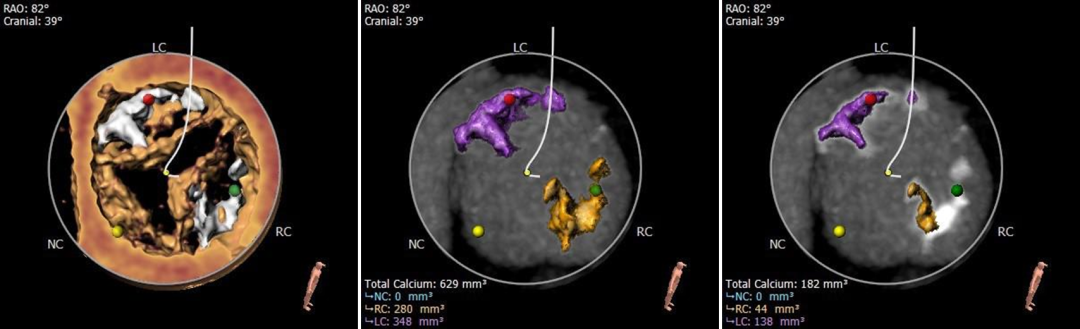

钙化分布

中度钙化,HU 600 629mm³,HU850 182mm³

三窦式,无冠窦发育畸形,窦内存在瓣叶间隔,钙化主要分布于左右窦窦内。

三叶式主动脉瓣,中度钙化,主要分布于左右窦窦底并延伸到瓣环-流出道水平,无冠窦发育畸形,窦内空间小;

该病例为三窦式,无冠窦先天发育畸形,窦内空间小并存在嵴样间隔,钙化主要分布在左右窦接近窦底位置并向下延伸,左窦瓣叶略长,可疑阻挡风险,术中需加以关注。

三叶式瓣,中度钙化,左右窦内钙化聚集向瓣环延伸,预估锚定难度适中,瓣膜植入后受团状钙化挤压存在瓣周漏风险;